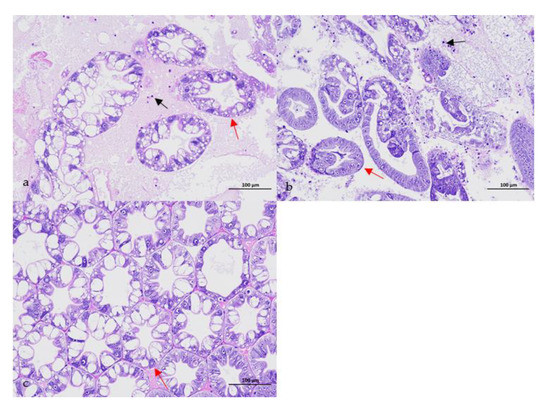

3.1. Confirmation of the Causative Pathogen